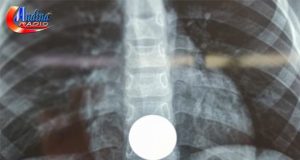

CHOTA: MEDICOS EXTRAEN MONEDA DE UN SOL QUE ATRAGANTO UN NIÑO...

El Hospital José H. Soto Cadenillas de Chota, en la región Cajamarca, logró una intervención médica crucial, al salvar la vida de un menor...